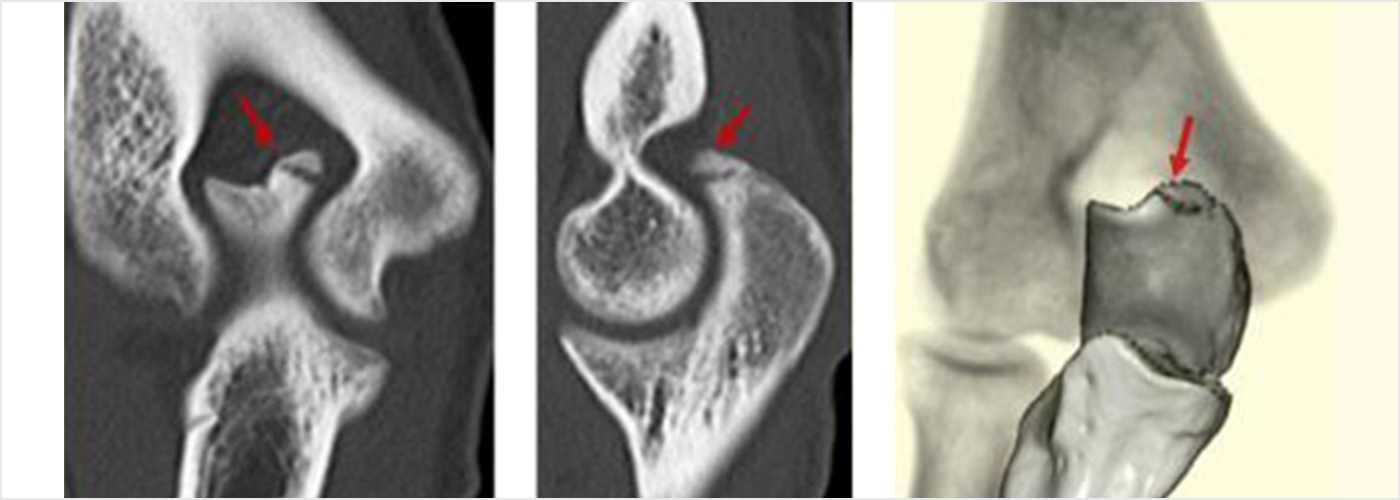

離断性骨軟骨炎(上腕骨小頭障害)

野球肘で最も重症になる障がいの1つです。ひどくなると関節軟骨の一部がはがれて関節ネズミとなったり、肘が変形して動きが悪くなったりします。初期に発見されれば投球禁止で治り、手術はしなくてもすむ場合が多いのですが、末期になると手術が必要となり、手術をしても肘の動きの制限や変形が残ってしまうこともあります。10歳前後で発症することが多いのですが、初期には自覚症状がないことが多く、13-17歳ごろにグラグラになった軟骨がはがれて痛みが出て初めて医療機関を受診されることもよくあります。 手術となった場合には骨の成長の度合い、病変の進行具合、病変の大きさなどにより手術方法が変わります。軟骨が安定している場合には軟骨を固定する手術を行う場合が多いです。軟骨がはがれている場合、病変が小さければ関節鏡を用いてはがれた、あるははがれかけている軟骨を摘出します(図4a)。病変の直径が1㎝以上であれば切開手術で膝の軟骨を病変部に移植します(図4b)。 最近全国各地で少年野球検診が行われるようになりましたが、一番の目的は離断性骨軟骨炎を早期に発見し、重症になる前に治療を行うことなのです。平成28年から多くの医師、理学療法士の協力により名古屋でも行われるようになりました。私も検診に参加し、エコーでのチェックを担当しました。およそ100人に1-2人の割合で発見されました。